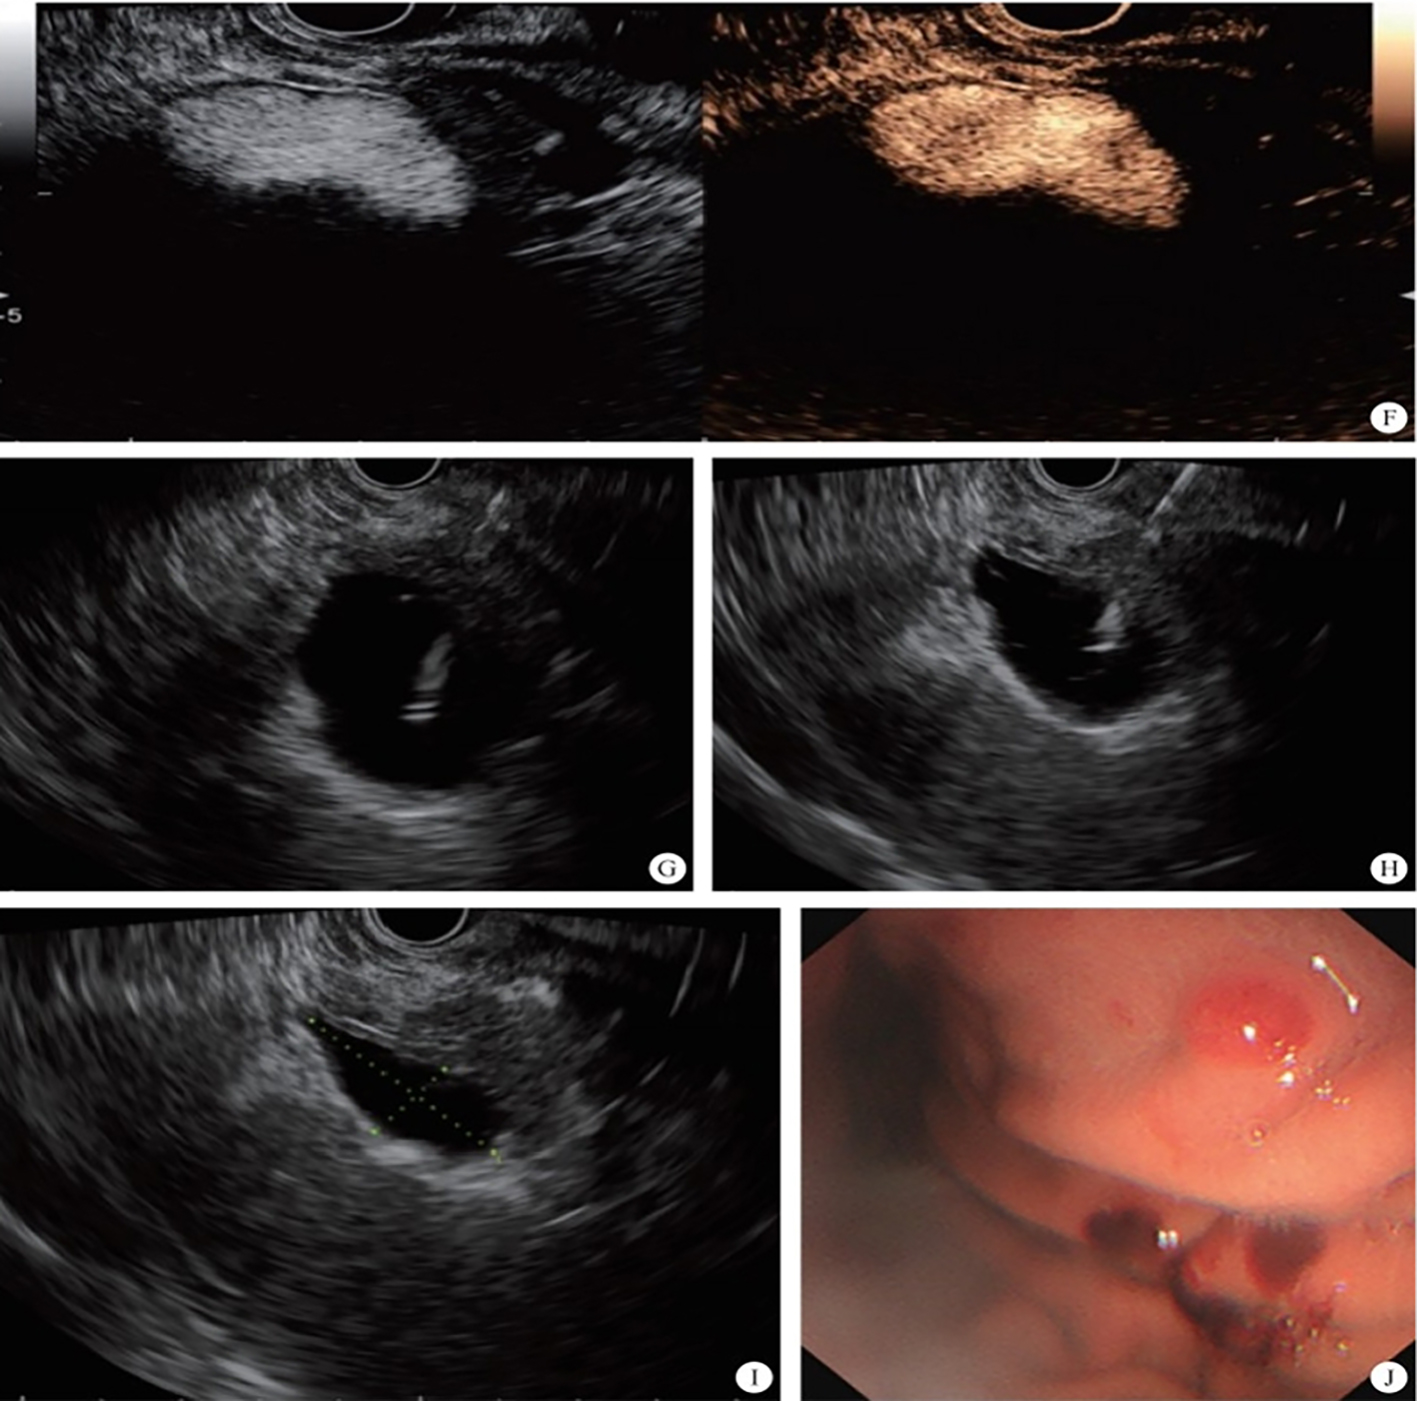

3. Development of the puncture channel. Over the past 10 years, endoscopic ultrasonography (EUS) has gradually become the third eye for endoscopists. Its combination with SMIS brings a new type model for the diagnosis and treatment of organic lesions outside the digestive tubes. For example, EUS-guided bile drainage (EUS–BD) and EUS-guided pancreatic duct drainage (EUS–PD) have been used as effective treatments after the failure of trans-nipple drainage; meanwhile the treatment strategy for acute necrotizing pancreatitis has also changed greatly. EUS-guided super minimally invasive drainage by gastric parietal puncture for pancreatic encapsulated necrosis and EUS-guided pancreatic cystic lesion puncture laurosinol ablation have become the mainstream treatment methods. In the future, SIMS operations like exploring and refining super minimally invasive drainage via a gastric puncture channel for suppurative cholecystitis, EUS-guided super minimally invasive gallstone extraction via a gastric puncture channel, EUS-guided portosystemic shunts and EUS-guided drainage of the chest, the abdomen and pelvic abscess, etc. will be the development directions.

FIG. 2.3 — SMIS through a puncture channel.